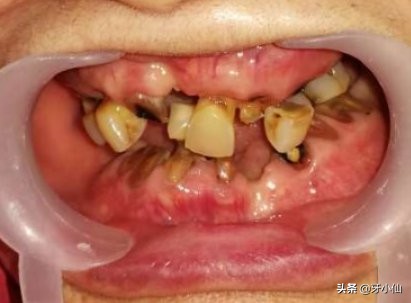

30 多岁的小伙子,被医生拔光了全口牙?

杭州28岁的姑娘,口里的牙齿像80多岁的老太太般的牙齿松松垮垮、根本吃不了东西?

28岁小姑娘,一口牙全不行了!

近日这几则爆出有小年轻就掉了全口牙的新闻在牙医圈中传开了。见过许许多多严重病患的医生仍然感到相当震惊和深深惋惜。

相对于龋齿、智齿发炎等常见的口腔疾病,牙周病是大家最容易忽视或者是陌生的,因为它的早期症状不易引起重视,患者较难察觉,或者只是以为口腔牙龈“上火”了而已。而且牙周病一开始不会让人们牙很疼,没有锥心的痛,人们就不会太在意,觉得无痛无病嘛,等到牙齿脱落了才后悔不已。